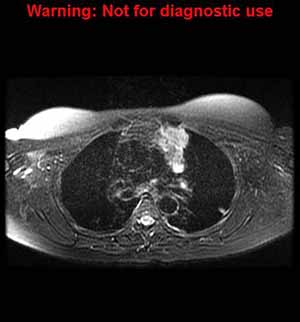

Please review the result by clicking on each image.

What is the most likely cause of the anterior mediastinal mass shown in these images? (You may select more than one option.)